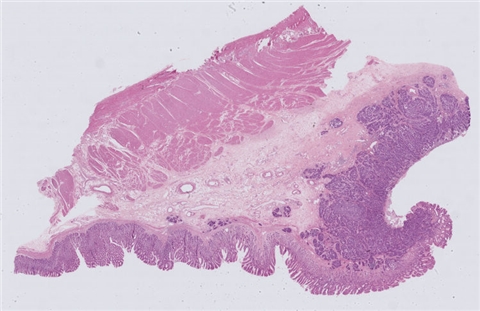

案例9 (6975)

性别:       年龄:41

患者详情: 患者于半年前无明显诱因出现大便带血,为暗红色血便,未见粘液脓血便,反复发作,无腹痛腹胀,伴大便次数增多,并大便不成形,逐渐变细,初未引起重视,亦未行相应治疗,后症状逐渐加重。为进一步诊治,2020年3月入住我院。 直肠指诊:括约肌紧张度:正常,狭窄:无,触痛:无,距离肛门口大约4cm可及一环直肠一周肿块,质硬,移动度差,无压痛,指尖稍可通过肿块,指套染血:有。 电子肠镜示:距肛门4cm直肠处可见一巨大新生物,中间凹陷,底覆污秽苔,环2/3腔生长,钳取6块送病理,余 结肠各段粘膜光整,血管纹理清晰,未见明显的溃疡、息肉。 活检病理示:恶性肿瘤。后行腹腔镜直肠癌根治术。

大体所见: 1、直肠癌肿物:已切开肠管一段,长10cm,一侧切缘周长4cm,另一侧切缘已缝合,长3cm,紧邻缝合切缘见一溃疡型肿物,大小4.5*4*3cm,肿物切面灰白灰黄色、质硬,与周围组织分界欠清,侵及全层。

2、上切缘:灰褐色黏膜组织一块,大小1*1*0.4cm。

3、下切缘:灰褐色黏膜组织一块,大小1.2*1*0.4cm。

免疫组化: 2002032-004#:CgA(弱+)、syn(+)、CD56(+)、 2002032-002#:CK(+)、TTF-1(+)、CD34 +、SMA(-)

医院: 赣南医学院第一附属医院